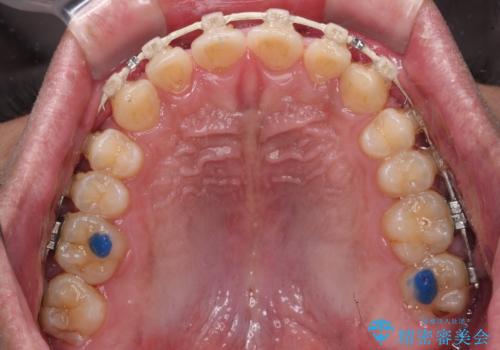

- 審美装置

- 1年5ヶ月

- 10-30回

マウスピース矯正の自己管理が面倒とのことで、ワイヤー矯正により治療を行うこととしました。

奥歯の咬み合わせは理想的な状態であったため、ワイヤー矯正でもインビザラインでも比較的容易に対応可能でした。